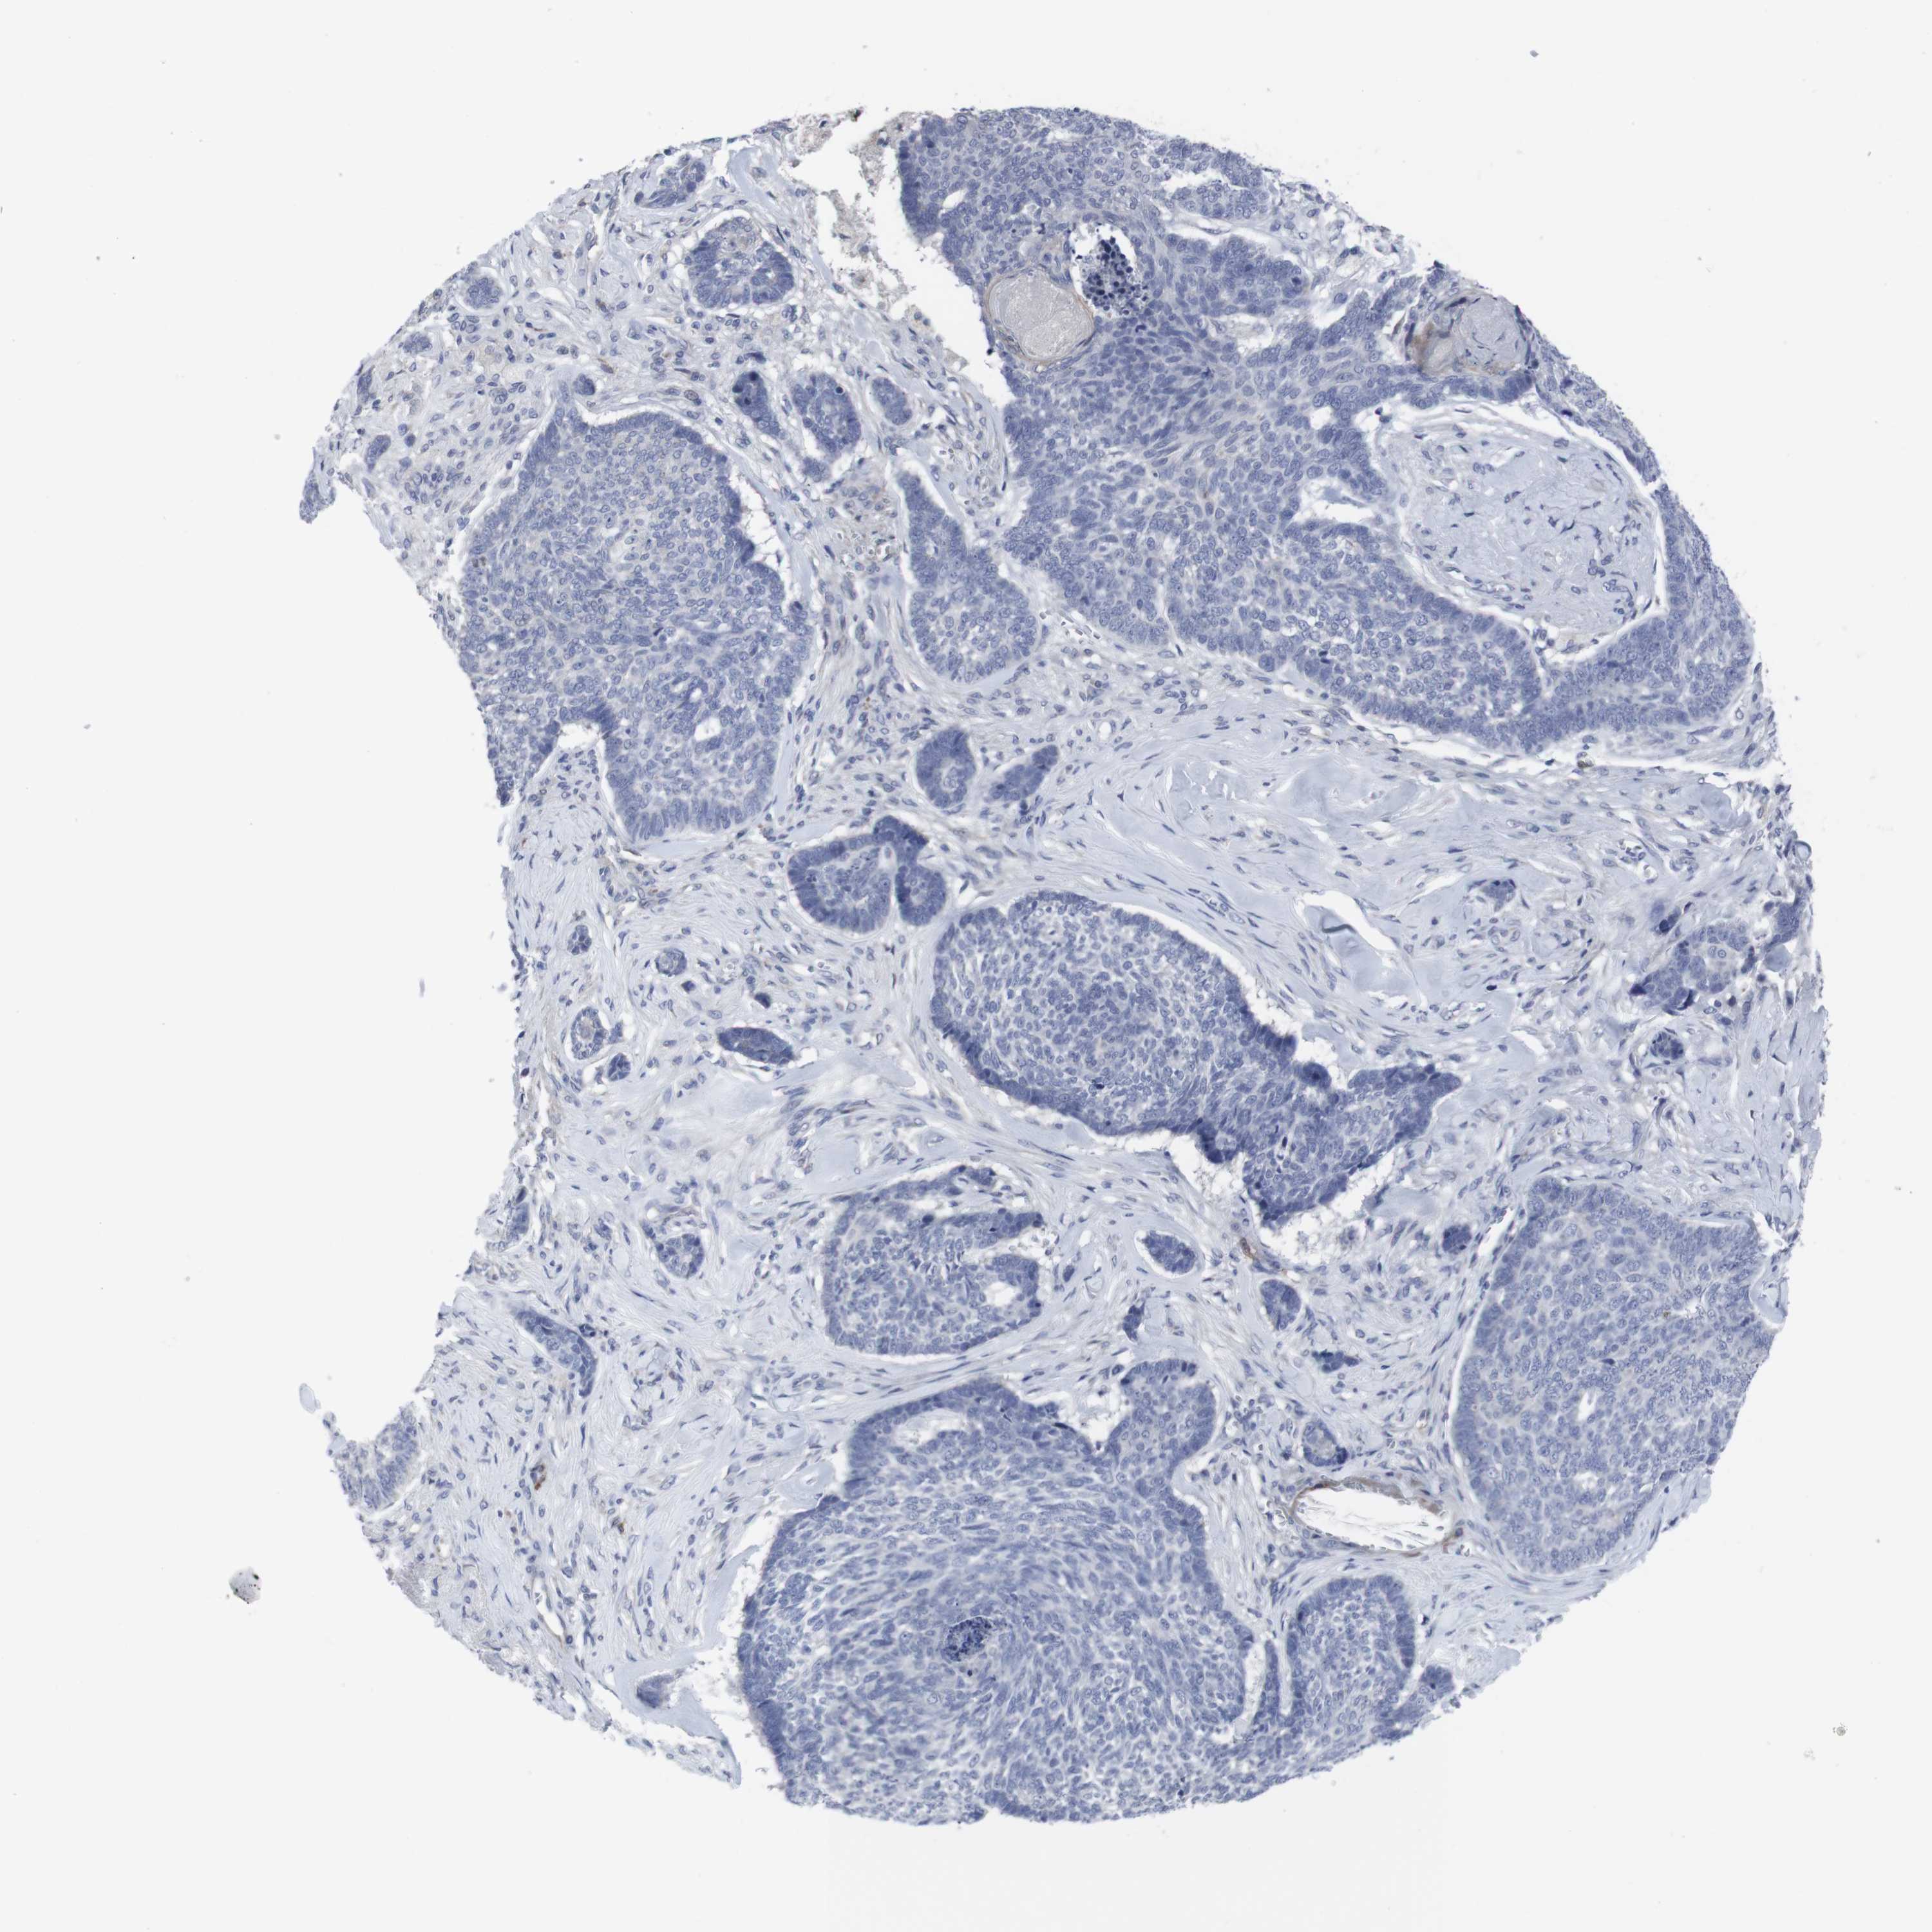

SKIN CANCER - Protein expressioni

A mouse-over function shows sample information and annotation data. Click on an image to view it in a full screen mode. Samples can be filtered based on level of antibody staining by selecting one or several of the following categories: high, medium, low and not detected. The assay and annotation is described here.

Each image is clickable and will lead to virtual microscopy that enables deeper exploration of all samples and also displays staining intensity scores, fraction scores and subcellular localization as well as patient and tissue information for each sample.

Antibody CAB080022

Staining

Low

Not detected

Intensity

Weak

Negative

Quantity

<25%

None

Location

Basal cell carcinoma